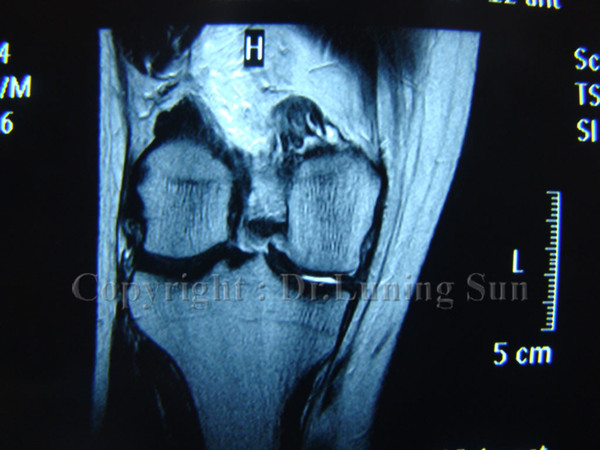

半月板损伤的诊断和治疗

600x450 - 76KB - JPEG